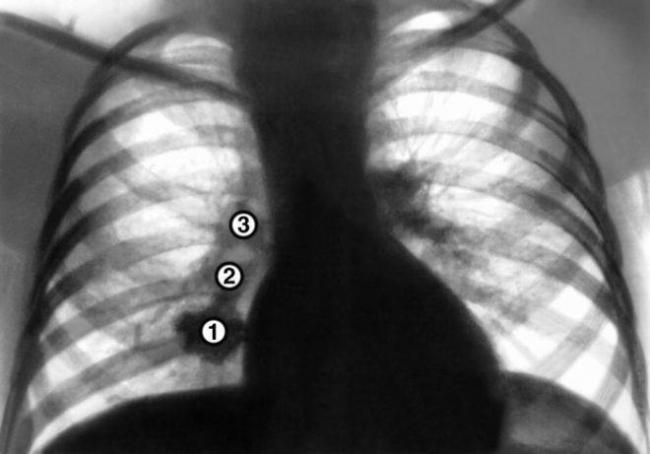

Провести аппаратным методом четкую диагностику заболевания не позволяет несовершенство оборудования. При прохождении рентгенографии легких трудно обнаружить очаговые изменения, размер которых не достигает 1 см. Интерпозиция анатомических структур делает невидимыми и более крупные образования.

Специалист предлагает больным пройти обследование с помощью компьютерной томографии. Она позволяет рассмотреть ткани под любым углом.